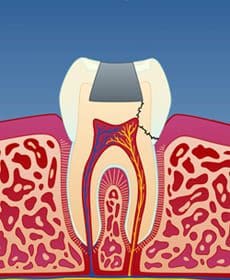

I tenner med store fyllinger er tannsubstansen rundt fyllingen svekket. Når man tygger, kan det etter hvert utvikles tynne sprekker i tannen. Disse sprekkene utvikler seg under fyllingen og forløper vanligvis på skrå bort fra tann-nerven (fig. 1). Infraksjonen kan imidlertid også gå inn til nerven (fig. 2) eller til og med dele tannen i to (fig. 3).